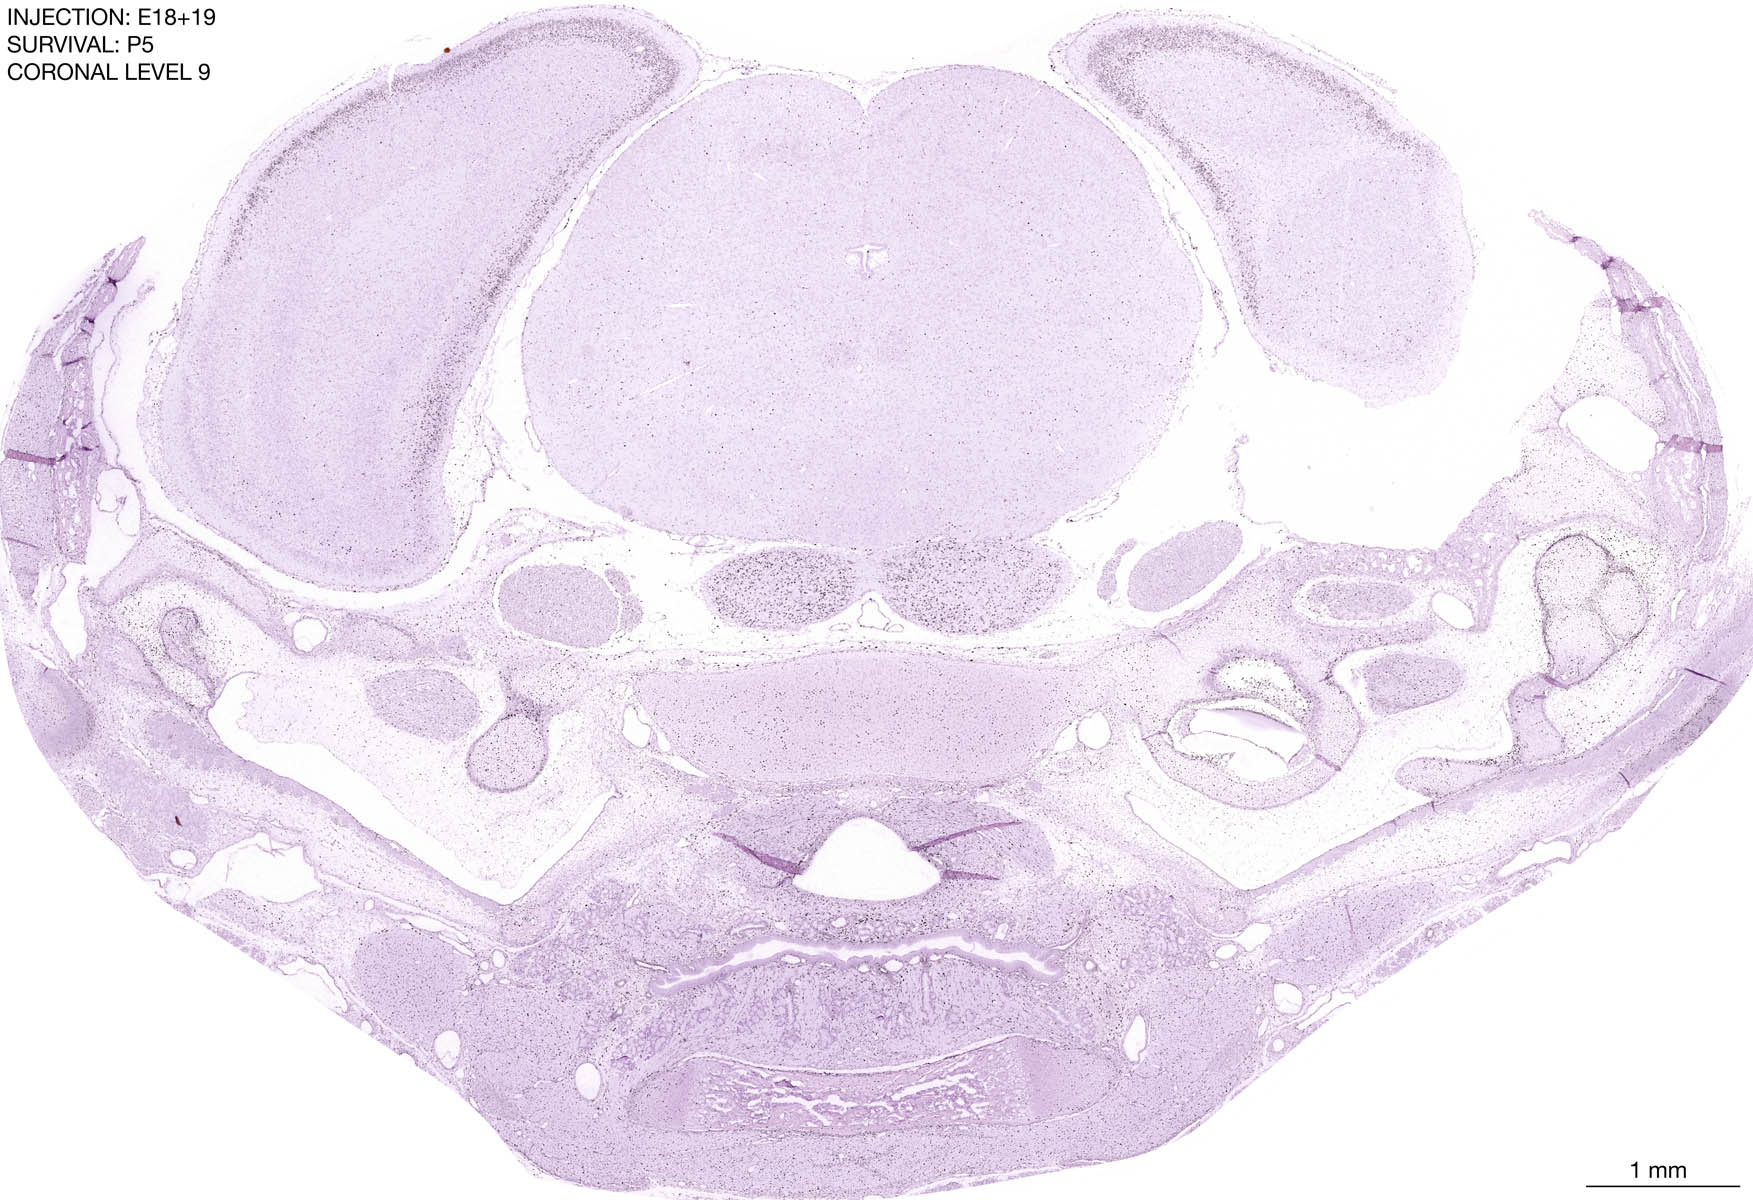

The images below are from the brain of a rat that was exposed to tritiated thymidine on E18+19 and survived to P5. Download: Large | High Res Download: Large | High Res Download: Large | High Res Download: Large | High Res Download: Large | High Res Download: Large | High Res Download: Large | High Res Download: Large | High Res Download: Large | High Res Download: Large | High Res Download: Large | High Res Download: Large | High Res Download: Large | High Res Download: Large | High Res Download: Large | High Res Download: Large | High Res Download: Large | High Res Download: Large | High Res Download: Large | High Res Download: Large | High Res Download: Large | High Res Download: Large | High Res Download: Large | High Res Download: Large | High Res